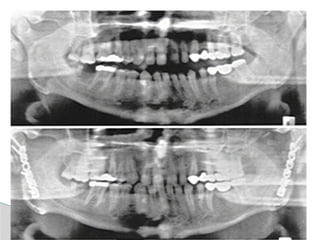

Conventional Radiology

At least 2 views at right angle to each other.

Mandibular series: PA, Lateral oblique or

panoramic, & Towne’s view (projects condyle

below mastoid process).

Conventional Radiology At least2 views at right angle to each other. Mandibular series: PA, Lateral oblique or panoramic, & Towne’s view (projects condyle below mastoid process). CT Significant displacement or dislocation, mechanical obstruction, mult trauma pt, & intracapsular fracture. MRI St injuries: effusion, visualization of disc. Imaging